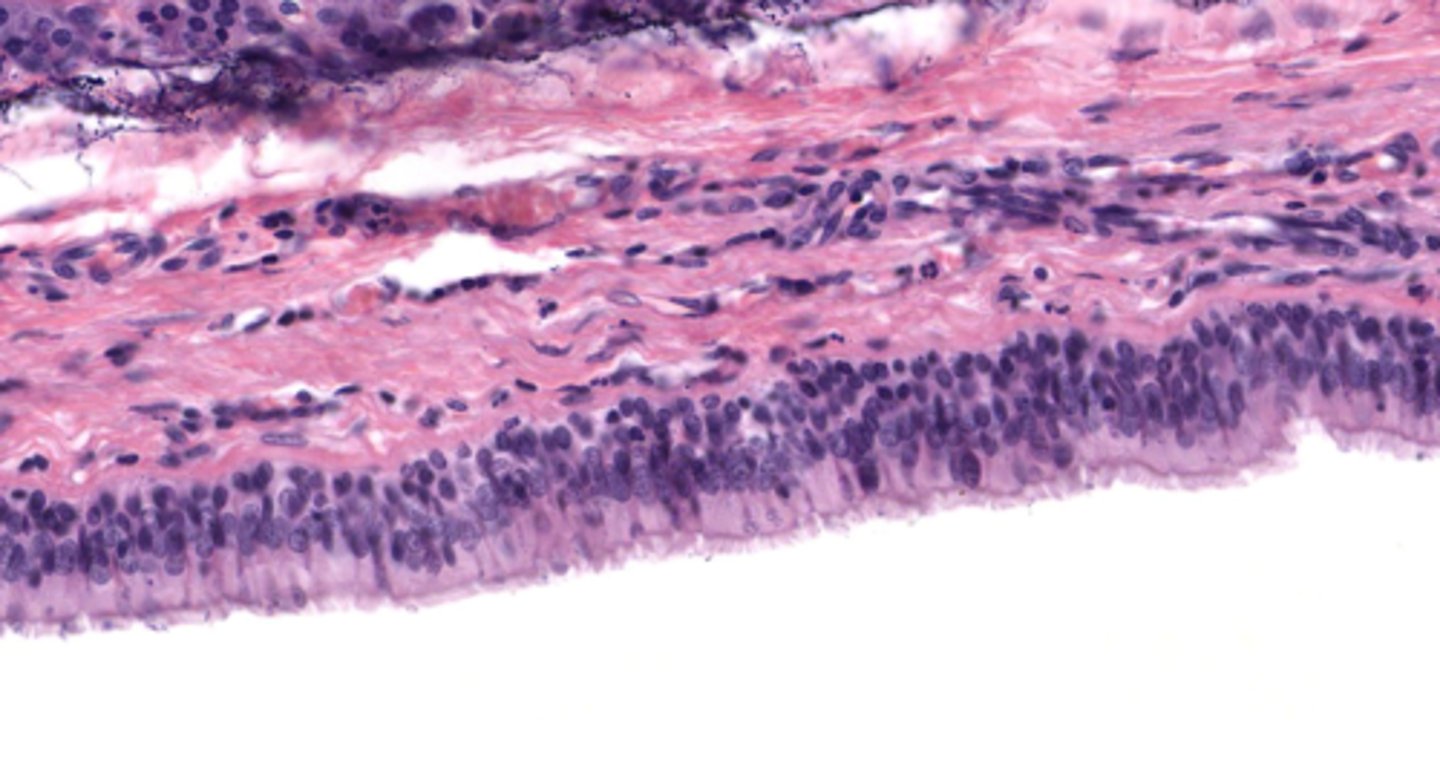

Classify the epithelium of the trachea

pseudostratified columnar ciliated with goblet cells

What is the name of this type of epithelium

respiratory epithelium

Identify the layer of the respiratory tract at 4

mucosa